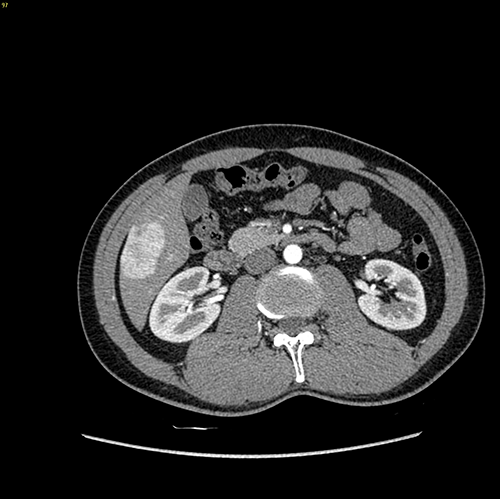

S6肝癌 胆囊结石--腹腔镜右肝部分切除 胆囊切除